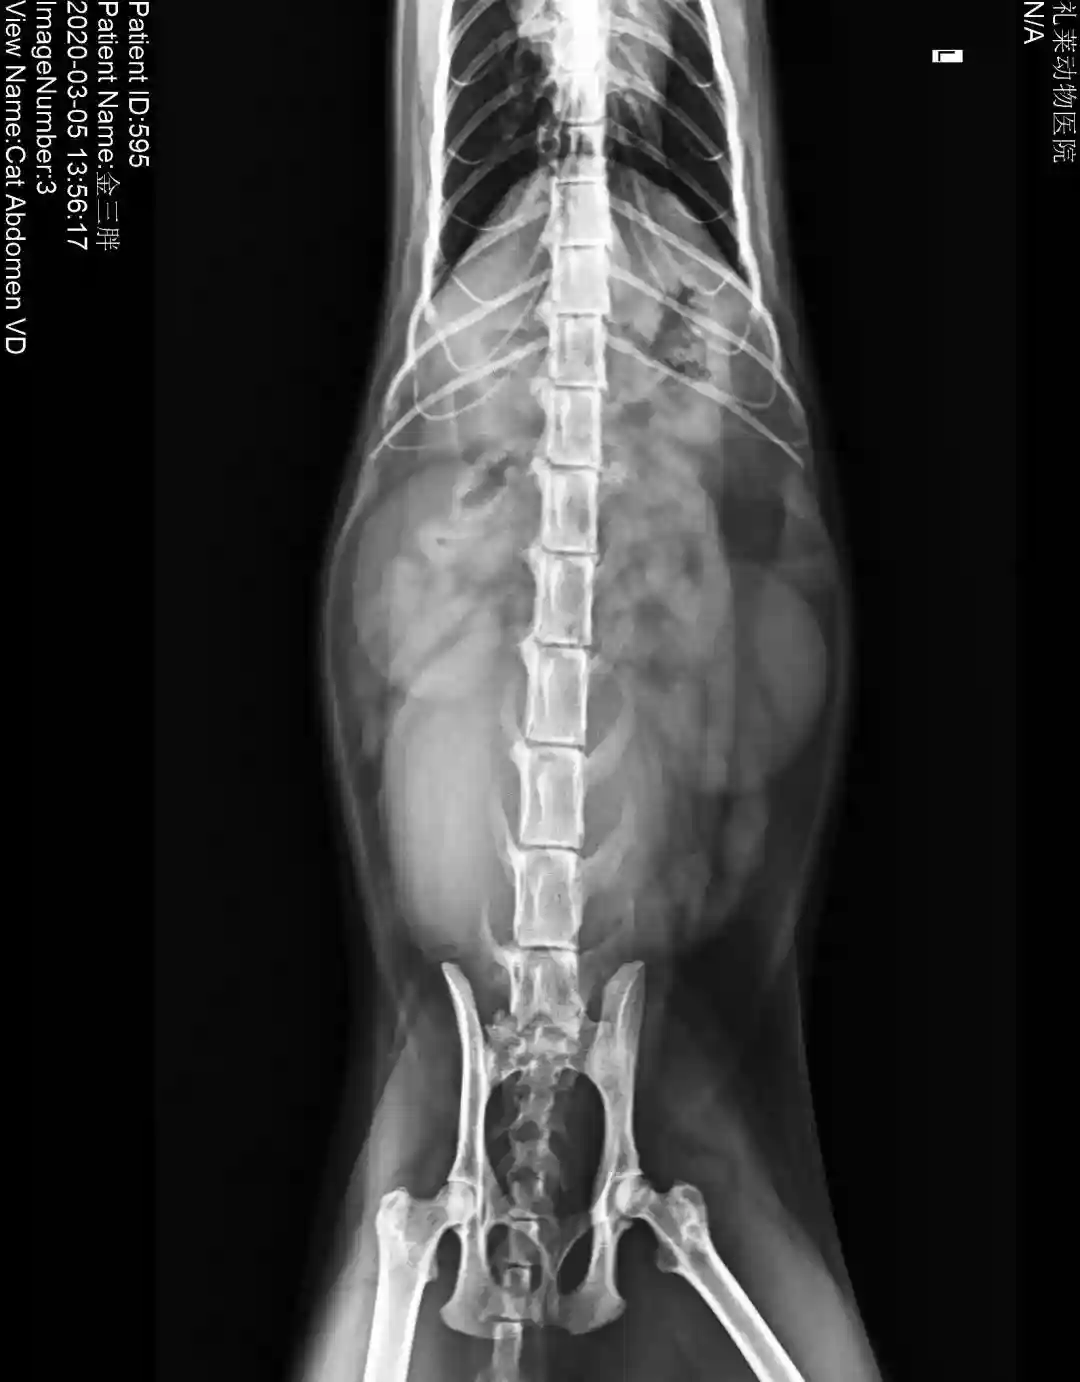

DR:

DR显示膀胱积尿较多,膀胱膨大,其他暂未见异常。